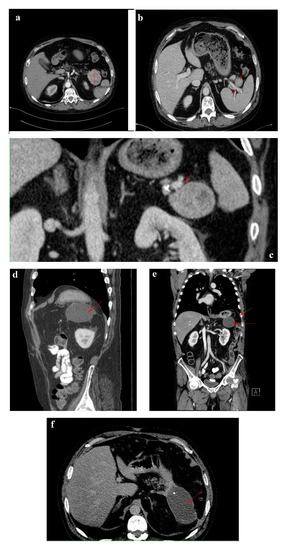

In February 2018, upon presentation to our department of endocrinology, the clinical examination revealed a middle-aged male patient unable to walk unassisted or without a frame, with severe bilateral hip arthralgia, slightly elevated blood pressure (150/90 mmHg) and tachycardia (heart rate = 110 bpm). The laboratory tests revealed normocytic normochromic anemia (Hb = 11 mg/dL), hypoproteinemia (5 g/dL), elevated inflammatory markers (ESR = 91 mm/h, fibrinogen = 668 mg/dL, high sensitivity CRP = 73.7 mg/L), high glycated hemoglobin (HbA1c = 7.6%), normal chromogranin A (CgA) and 5-hydroxyindoleacetic acid (5-HIAA), and elevated plasma glucagon levels (2130 ng/L, N < 209) that confirmed the positive diagnosis of glucagonoma syndrome. Biochemical screening for MEN 1 syndrome was negative (serum calcium = 8.3 mg/dL, PTH = 32.62 pg/mL, 25 hydroxy vitamin D = 27.27 ng/mL, prolactin = 12 ng/mL, IGF1 = 114 ng/mL). A multiphasic contrast-enhanced CT diagnosed a 35/44 mm tumor with heterogenous texture located in the pancreatic tail, multiple peritumoral nodules suggestive of locoregional metastases, two incompletely consolidated fractures at the sixth and seventh ribs, and a reduction in bone density and the height of the thoracolumbar vertebras (Figure 3a–c).

The six month follow-up in September 2018 was uneventful, with the glucagonoma syndrome well controlled on SSA therapy, normal plasma CgA, decreasing glucagon levels (863 ng/L) and stable disease on CT (Figure 3d). It is important to mention that the patient received treatment with vitamin K antagonists for the deep vein left leg thrombosis and displayed high fluctuations in INR values. Despite our plan for the tumor surgical resection, the preoperative biological check-up revealed an INR value of 14, which prompted intravenous phytonadione administration. The INR reached the therapeutic range; however, the patient developed sagittal sinus thrombosis that was eventually favorably managed by the department of neurology.

In October 2019, a follow-up abdominal multiphasic contrast-enhanced CT showed small-scale tumor progression and the patient was scheduled for surgery again (Figure 3e). The echocardiography performed during the preoperative cardiologic evaluation revealed hypokinesia of the ventricular septum; akinesia of the basal segment of the inferior wall; akinesia of the medium segment of the inferolateral, lateral and anterior walls; and severe left ventricular dysfunction with an ejection fraction of 28%. Coronary angiography uncovered trivascular atherosclerotic disease, and a percutaneous angioplasty with stent implantation was performed. The surgical intervention was postponed again.

Regrettably, in the spring of 2020 the COVID-19 pandemic reached our country and follow-up was possible only in July 2020, when, despite clinical control, the tumor (52/45 mm) and the peritumoral nodules had progressed; however, no hepatic or bone metastases were detected during morphological imaging (Figure 3f). As expected, we attempted surgery once more. This time, the patient was infected with SARS-CoV-2 and, by an unexpected fortunate chance, he had a completely asymptomatic infection.

In January 2021, a follow-up CT reconfirmed locoregional tumor progression without apparent distal metastasis (Figure 6a–c), and a distal pancreatectomy and splenectomy were performed with a favorable outcome. An open approach with a bilateral subcostal incision was chosen. After opening the abdomen, a thorough examination of the peritoneal cavity was performed. We discovered a 6/5 cm tumor in the tail of the pancreas, without any vascular or retroperitoneal involvement. No liver or peritoneal metastases were present. We opted for a distal spleno-pancreatectomy in a standard fashion with a clockwise approach and individual splenic artery and vein ligation, ensuring a proper oncological safety margin on the pancreatic body. The pancreas was transected using monopolar cautery (Figure 7a) with pancreatic duct identification and clipping (Figure 7b), and the pancreatic stump was double sutured: the first was an overlapping horizontal mattress suture, and the second was a figure-eight suture (Figure 7c). Two drainage tubes were placed, the abdomen was closed, and the specimen was sent for pathology examination (Figure 7d). The postoperative course was uneventful. We checked the amylase level in the drained fluid on the third postoperative day and it was normal, which allowed us to exclude the pancreatic fistula. The abdominal ultrasonography performed did not show any collections, and the drainage tubes were removed. The patient was discharged on the eighth postoperative day.

Figure 3. 1 February 2018 CT scan: (a) axial image without contrast showing a round solid mass with microcalcification in the tail of the pancreas; (b) arterial phase coronal reconstruction showing a hypervascular mass with satellite nodules situated in the pancreatic tail; and (c) axial image, arterial phase showing a 35/44 mm tumor in the pancreatic tail. September 2018 follow-up CT: (d) axial image, arterial phase showing stable disease. October 2019 follow-up CT: (e) axial image, arterial phase showing inhomogeneous contrast enhancement and small-scale tumor progression. July 2020 follow-up CT: (f) axial image, arterial phase showing evident tumor mass progression.

Figure 6. Follow-up CT January 2021: (a) axial image-tumor progression; (b) axial venous phase with no vascular invasion; (c) coronal reconstruction venous phase, shows the fat plan between the mass and the vascular structures, indicating that the lesion is operable. Follow-up CT April 2021: (df) venous phase sagittal, coronal and axial reconstructions, respectively, showing fluid collection after the surgical removal of the pancreatic masses and the spleen. Red arrows and line indicate the lesions described in the figure legend; further information may be redundant.